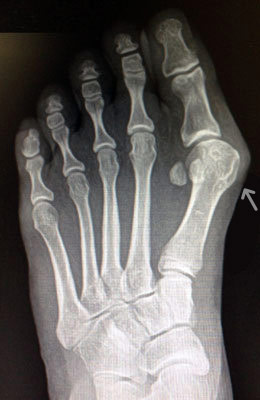

Osteotomy Bunionectomy, Hammertoe Correction and Plantar Plate Repair after

Osteotomy Bunionectomy, Hammertoe Correction and Plantar Plate Repair

Ziba is a 67-year-old female with years of foot pain. Her bunion was so severe she had placed a lot of weight on her 2nd and 3rd toes which had become totally dislocated (as shown in x-rays). Ziba required an osteotomy bunionectomy, hammertoes corrections with our Ossio™ implant and metatarsal phalangeal joint relocation and plantar plate repair. Ziba was allowed to place weight on her foot right after surgery and was back in shoes at 8 weeks. An amazing result considering how difficult toe relocation can be. After picture taken immediately following surgery.